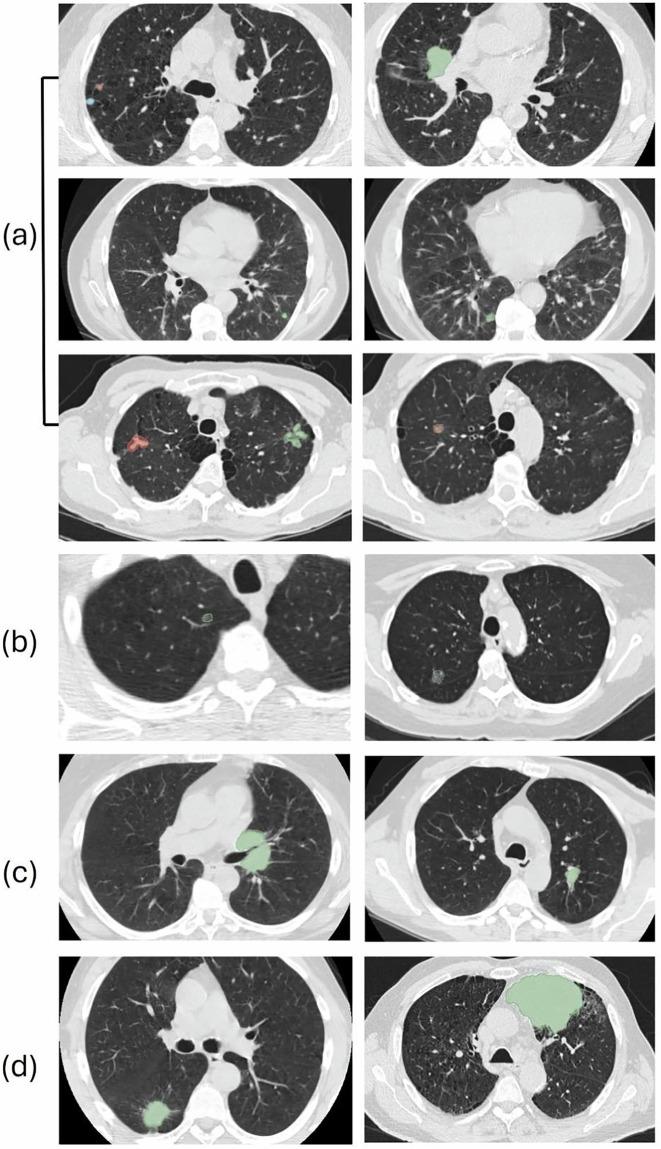

Low-dose computed tomography (LDCT) is the most effective tools for early detection of lung cancer. With advancements in artificial intelligence, various Computer-Aided Diagnosis (CAD) systems are now supported in clinical practice. For radiologists dealing with a huge volume of CT scans, CAD systems are helpful. However, the development of these systems depends on precisely annotated datasets, which are currently limited. Although several lung imaging datasets exist, there is only few of publicly available datasets with segmentation annotations on LDCT images. To address this problem, we developed a dataset based on NLST LDCT images with pixel-level annotations of lung lesions. The dataset includes LDCT scans from 605 patients and 715 annotated lesions, including 662 lung tumors and 53 lung nodules. Lesion volumes range from 0.03 cm to 372.21 cm, with 500 lesions smaller than 5 cm, mostly located in the right upper lung. A 2D U-Net model trained on the dataset achieved a 0.95 IoU on training dataset. This dataset enhances the diversity and usability of lung cancer annotation resources.

低剂量计算机断层扫描(LDCT)是早期检测肺癌最有效的工具。随着人工智能的发展,目前临床实践中支持各种计算机辅助诊断(CAD)系统。对于处理大量CT扫描的放射科医生来说,CAD系统很有帮助。然而,这些系统的开发依赖于精确标注的数据集,而目前此类数据集有限。尽管存在几个肺部影像数据集,但只有少数公开可用的LDCT图像分割标注数据集。为了解决这个问题,我们基于NLST LDCT图像开发了一个具有肺部病变像素级标注的数据集。该数据集包括来自605名患者的LDCT扫描和715个标注病变,其中包括662个肺肿瘤和53个肺结节。病变体积范围从0.03立方厘米到372.21立方厘米,500个病变小于5立方厘米,大多位于右上肺。在该数据集上训练的二维U-Net模型在训练数据集上实现了0.95的交并比。这个数据集增强了肺癌标注资源的多样性和可用性。